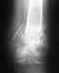

Снимок только в одной проекции, для более полной оценки ситуации надо и фас увидеть. И в первую очередь узнать о клиническом статусе - жалобы, ось, длина, амплитуда движений в колене, опоросопособность, потребность в дополнительной опоре?